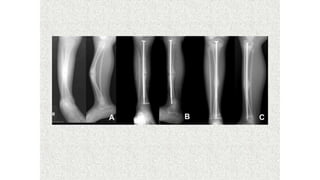

This document discusses a disease and its investigation and management. It begins by introducing Dr. Aniket Wankhede from MGIMS Sevagram and asks what the disease is. It then asks how the disease happens and discusses its causes. Next it asks how the disease appears on x-rays and describes symptoms some people experience living with it. Finally, it asks how the disease will be investigated and managed.